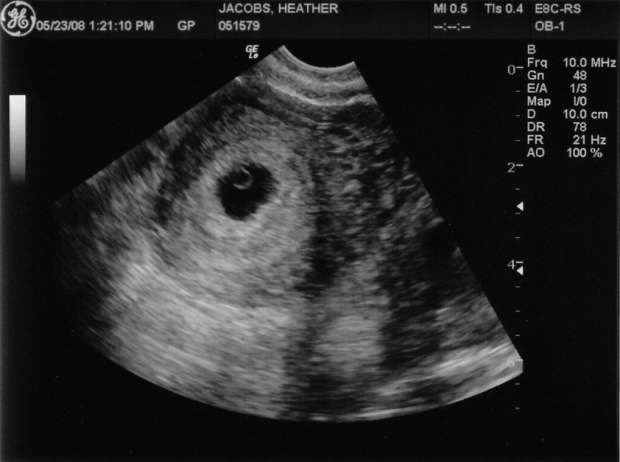

УЗИ на 4 неделе беременности

Ультразвуковое исследование на четвертой неделе беременности выполняется с использованием трансвагинального датчика. Это обследование позволяет выявить внематочную беременность, которая на данном сроке проявляется в виде небольшого черного кружка.

При нормальном течении беременности на УЗИ можно заметить значительное расширение сосудов в матке. Это свидетельствует о том, что организм женщины активно готовится к поддержке новой жизни.

На этом этапе эмбрион еще не виден, однако в конце четвертой недели можно обнаружить кольцо диаметром 2-3 мм. Это желточный мешочек, который обеспечивает питание зародыша. Всего через неделю на этом кольце станет виден и сам эмбрион.

Кроме того, во время исследования можно заметить желтое тело. В нормальном менструальном цикле оно достигает максимального размера (около 20 мм) на 21 день, после чего начинает уменьшаться. Если же яйцеклетка была оплодотворена и эмбрион внедрился в стенку матки, желтое тело продолжает расти и на четвертой неделе беременности достигает размера 30 мм.

Фото УЗИ по неделям беременности помогут вам следить за развитием вашего малыша.